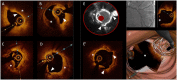

Editorial: Intracoronary Imaging Guidance for Percutaneous Coronary Interventions

Keywords: IVUS; NIRS; OCT; PCI; intracoronary imaging.